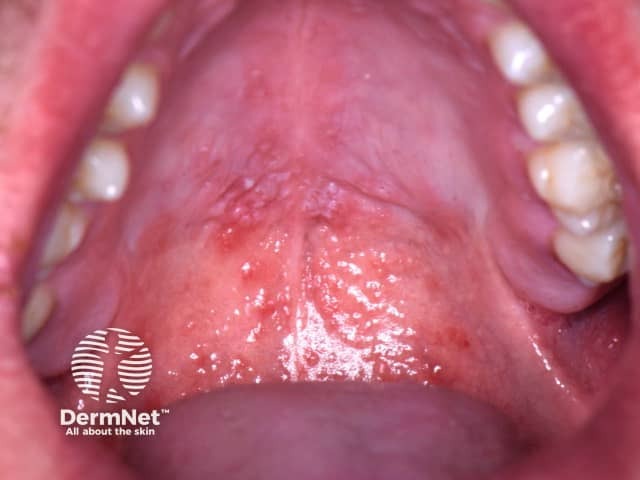

Stomatitis in HFMD

Oral hand, foot, and mouth disease